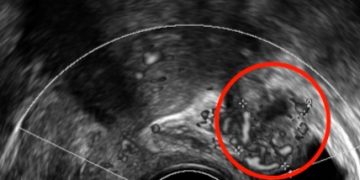

Leggi di piùCari soci, questo mese un nuovo video "How to do", sulla diagnosi ecografia di patologia tubarica nel contesto della malattia infiammatoria pelvica. Grazie a Debora Verri! Il video è accessibile...